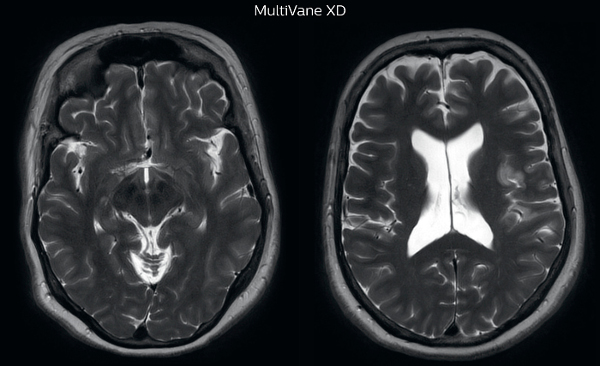

“MultiVane XD is especially useful for imaging patients with diseases that cause white matter changes on T2-weighted images”

“Motion artifacts can obscure subtle findings, make image interpretation more difficult and decrease diagnosis confidence. For example, when imaging the cerebellum or brain stem, or when looking for subtle multiple sclerosis (MS) lesions, motion can be problematic,” says Dr Nickerson. MultiVane XD motion-free imaging delivers diagnostic images even in the case of severe patient motion. A more relevant patient group is one with typical small artifacts related to moderate motion like an occasional cough. The absence of those artefacts brings forth better day-to-day diagnostic confidence. MultiVane XD works in multiple orientations and for various contrasts, such as T1-weighted, T2 weighted and FLAIR. Trevor Andrews, PhD, explains that the team compared motion artifacts seen in the brain with MultiVane XD and with T2-weighted TSE. “In nine out of the ten datasets in our studywe saw clear improvementswith MultiVane XD, while in the tenth dataset image qualitywas comparable. The MultiVane XD sequence is now used in the majority of patients that present at UVM for brain MRI.”

Motion-free imaging of white matter changes with MultiVane XD

“We saw MultiVane XD provide remarkable improvement, not only for artifacts caused by patient motion, but also for the extent of pulsation artifacts in the basal cisterns. Based on these results, we have added the MultiVane XD sequence to our brain studies,” says Dr. Nickerson. “MultiVane XD is especially useful when imaging patients with diseases that cause white matter changes on T2-weighted images, such as MS, small vessel disease, vasculitis and sarcoidosis,” says Dr. Nickerson. “Many of these are only visible on T2-weighted or FLAIR images, and sometimes aren’t even seen with FLAIR images. However, when using MultiVane XD and we don’t see any motion on the rest of the scan, but still do see a signal abnormality, we can probably attribute that to a real disease process, rather than an artifact.”

MRI motion artifact reduction in brain

The images made with MultiVane XD show significant reduction in motion artifact compared to the T2-weighted images without MultiVane below them. Scanned on Ingenia 3.0T